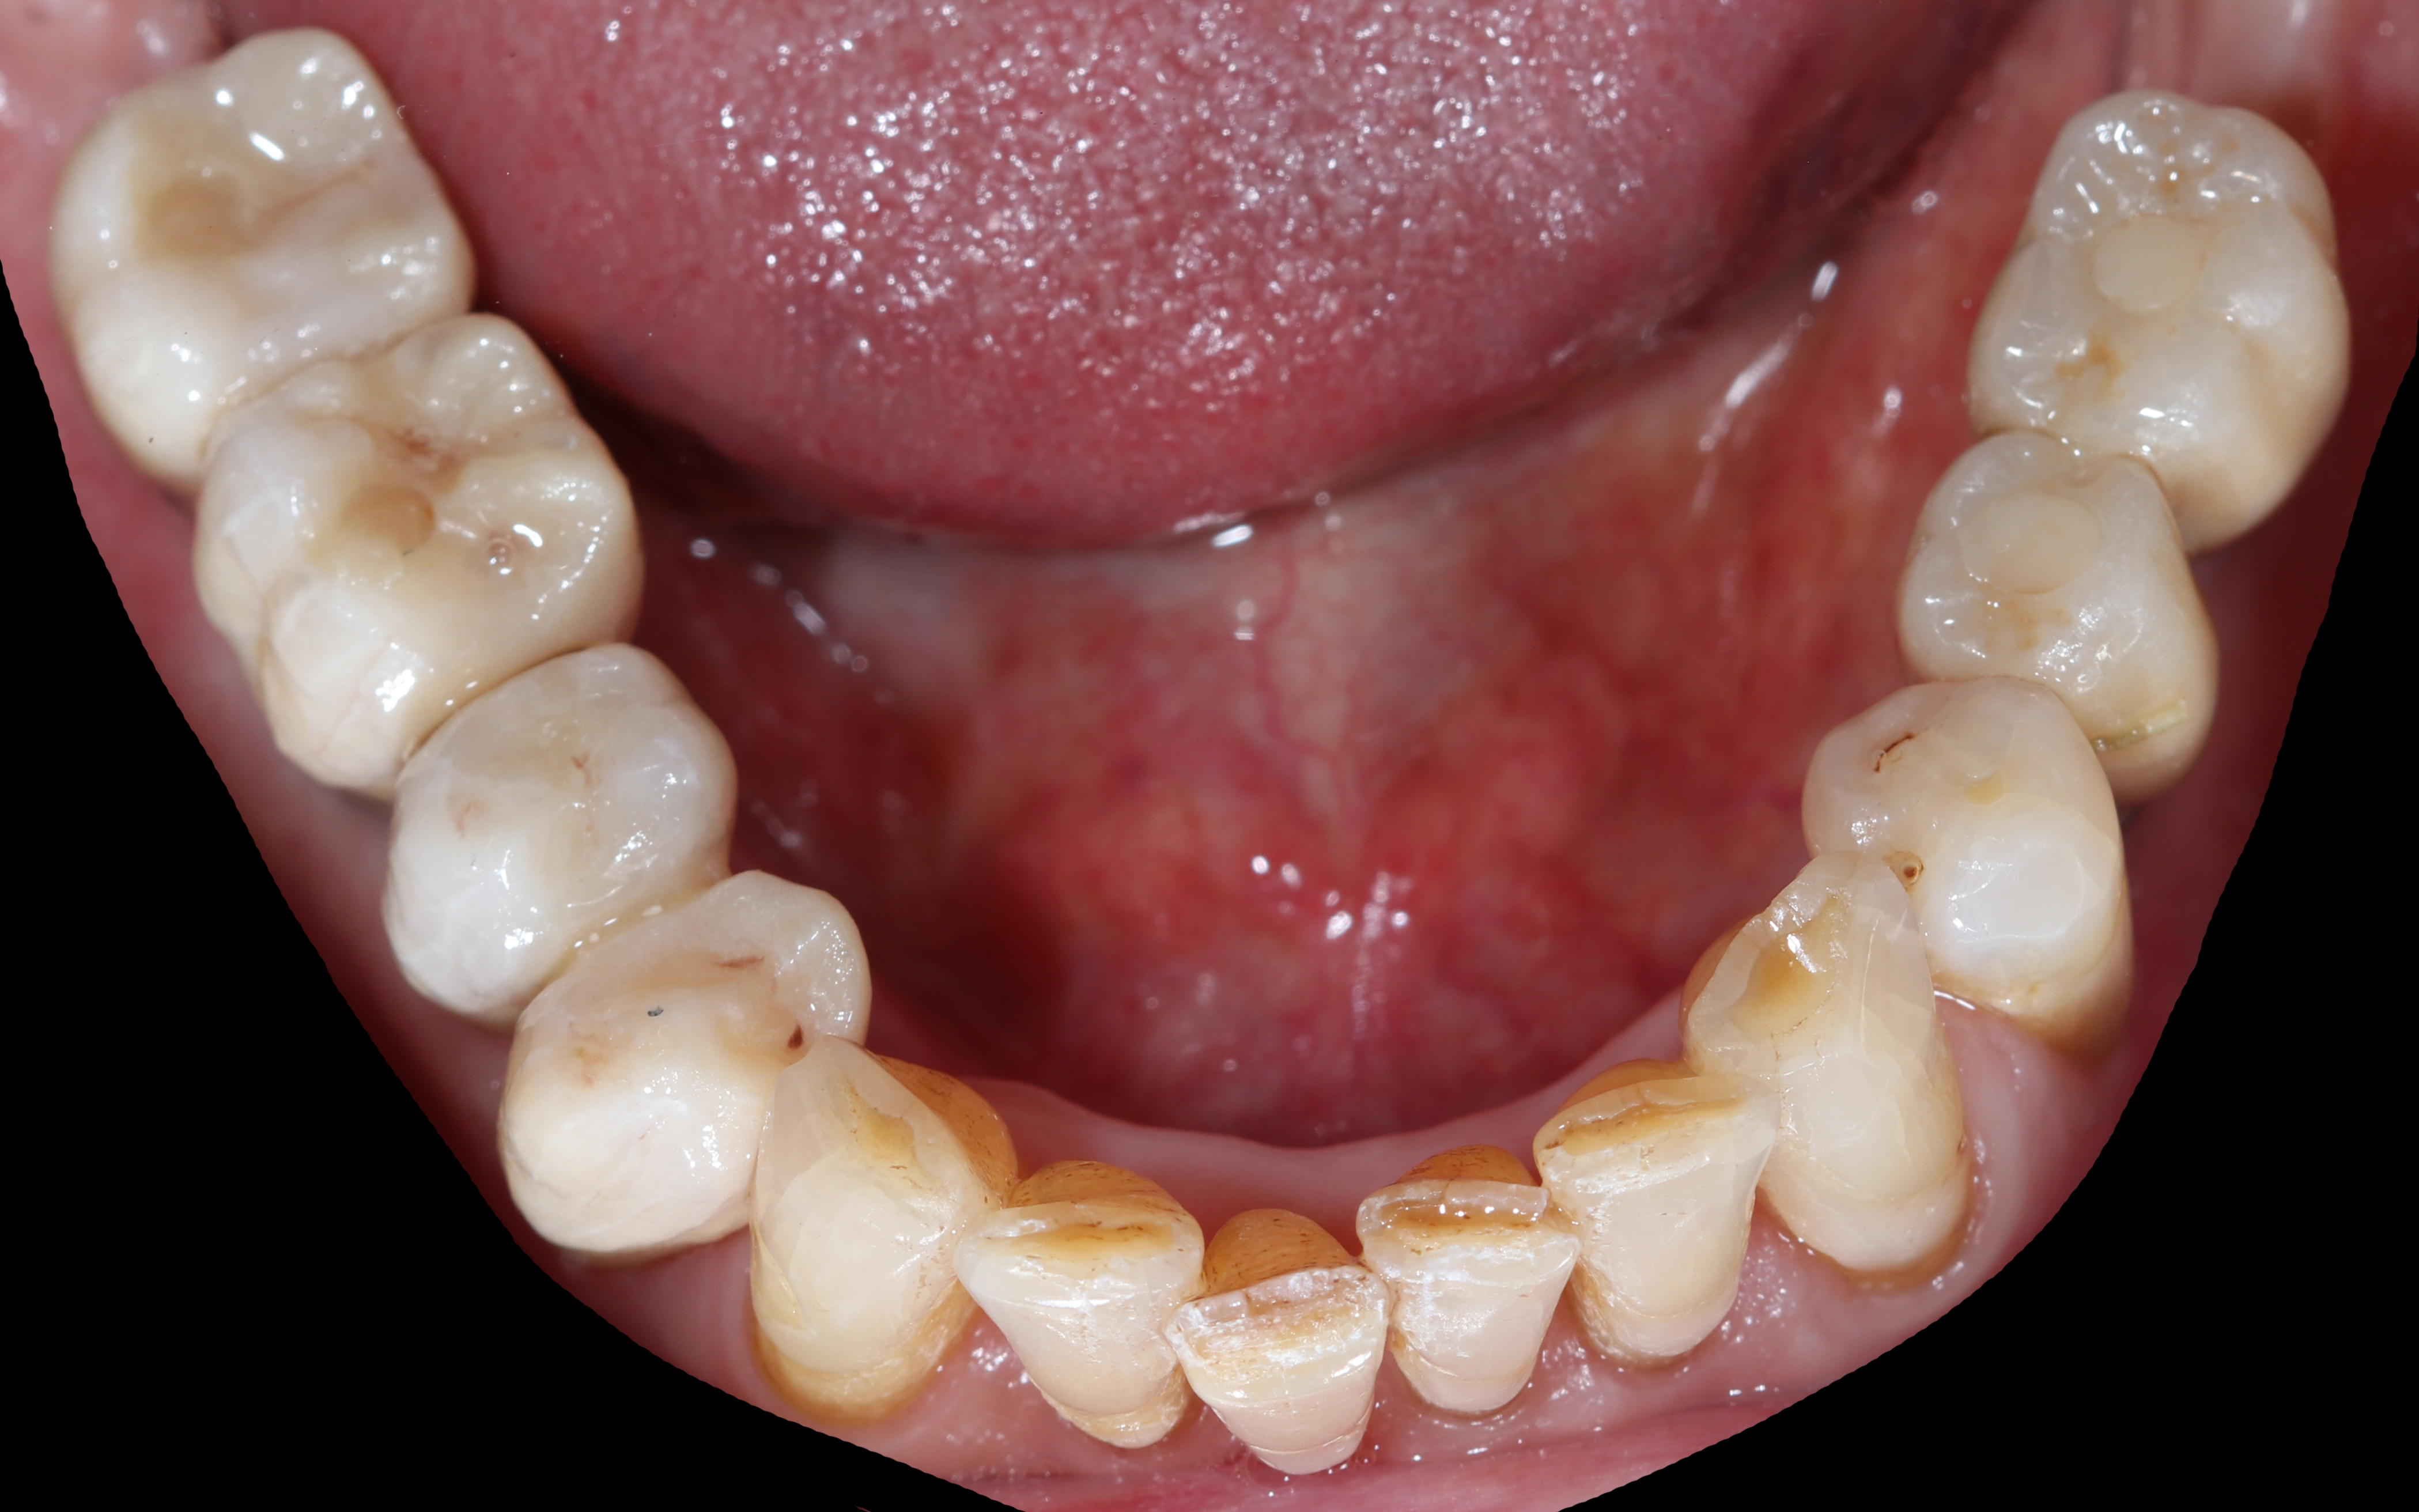

Αρχική κατάσταση - Μασητική άποψη